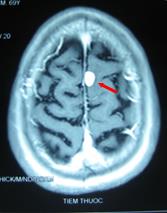

+ Kết quả chụp cộng hưởng từ sọ não: Khối u não vùng đỉnh trái, kích thước 1,7×2,3cm, có phù não xung quanh.

- Thực thể: khối u não di căn biến mất trên phim chụp cộng hưởng từ, u phổi nhỏ lại trên phim chụp cắt lớp vi tính.